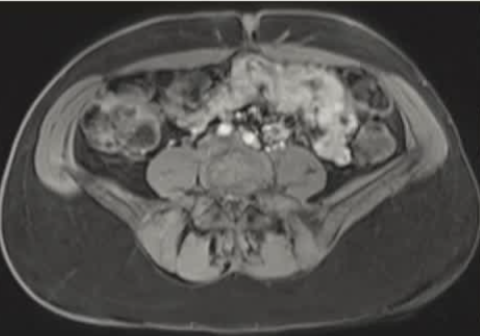

影像引导方式:超声和横断面成像(CT或MRI)结合是最常用的影像引导方式(10/16,62.5%)。

保护措施:几乎所有干预都需要辅助保护措施,其中水分离术(13/16,81.3%)和水分离术与温盐水填充手套的皮肤保护结合(9/16,56.3%)是最常见的保护措施。

| 腹壁下病变 | MRI引导下 冷冻消融。装有热水的手套在皮肤表面保护皮肤 |